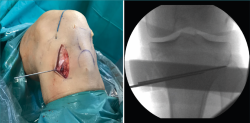

Figura 1. A: colocación del paciente con rodilla a 90° de flexión. Se marca la incisión de aproximadamente 4-6 cm que servirá para la extracción de los isquiotibiales y la osteotomía tibial alta; B: extracción de isquiotibiales para realizar la plastia.

Se marca sobre la piel la línea de incisión de 4-6 cm en la cara medial de la tibia proximal, aproximadamente 1,5 a 2 cm por debajo de la interlínea articular (Figura 1A). Una de las ventajas de esta osteotomía es que no precisa disecar e inestabilizar el ligamento colateral medial (LCM). El corte se realiza entre las dos inserciones del LCM y la placa se coloca por encima de este ligamento. De esta manera, la rodilla sigue estable aunque se decida realizar una retirada de la placa una vez consolidada la osteotomía.

Figura 2. Colocación de aguja guía: punto de entrada en la unión metafisodiafisaria tibial dirigida hacia la cabeza del peroné.

Una vez disecado el plano subcutáneo, se identifica la pata de ganso y se extraen los isquiotibiales según la técnica habitual de cada cirujano (Figura 1B). Bajo control radioscópico, se coloca la aguja guía aproximadamente medio centímetro por encima de la pata de ganso orientada hacia la cabeza del peroné, según la técnica clásica de osteotomía biplanar (Figura 2). Se marcan los cortes de la osteotomía biplanar y se realiza primero el corte vertical por encima de la tuberosidad tibial, con una inclinación de aproximadamente 120° respecto a la osteotomía de apertura llegando hasta la cortical lateral (Figura 3).